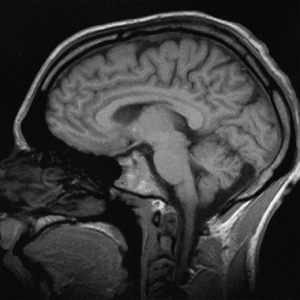

II         FMRI allows neuroimaging of specific brain activity with mapped functionalities

5S on the brain left posterior view.png

VIII     Activation of middle temporal gyrus with more organization

a.       pattern recognition portion of the brain